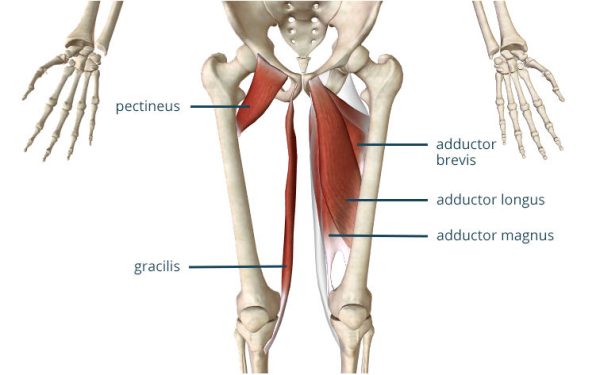

Анатомия и Функции Мышцы Adductor Magnus